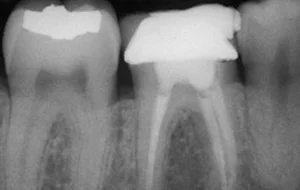

• This is followed by disinfection and shaping of pulp canals. The infected pulp is cleared out completely, canals are shaped and cleaned. Thorough disinfection is achieved.

• Clean and disinfected canals are then sealed and filled with an inert rubber-like filling material known as Gutta-Percha.

• The very last step is restoration & crown. The crown portion of the tooth cavity is then restored with a filling, followed by a Cap/Crown cementation.